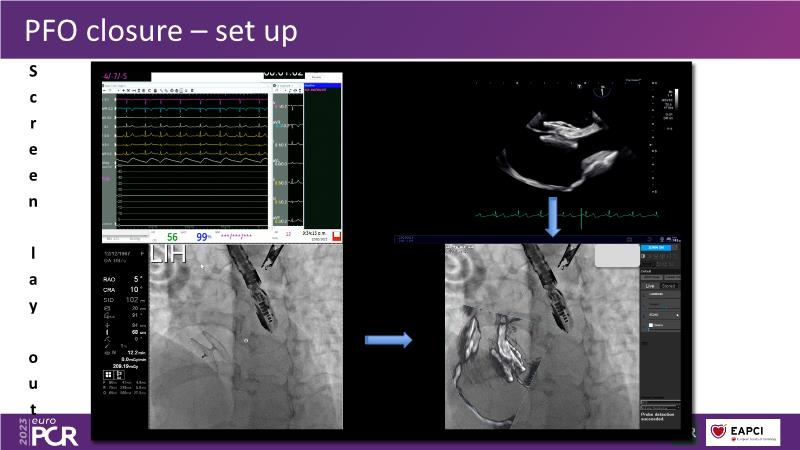

In this session, watch the case of a 56-year-old man with HTN, DM, stable CAD, PFO and previous ischaemic stroke, who presented with severely calcified CTO lesion on proximal LAD and significant mid-RCA lesion, and find out how he was treated LIVE... among others!

- To discuss the impact of deep learning-assisted fusion images across various imaging modalities